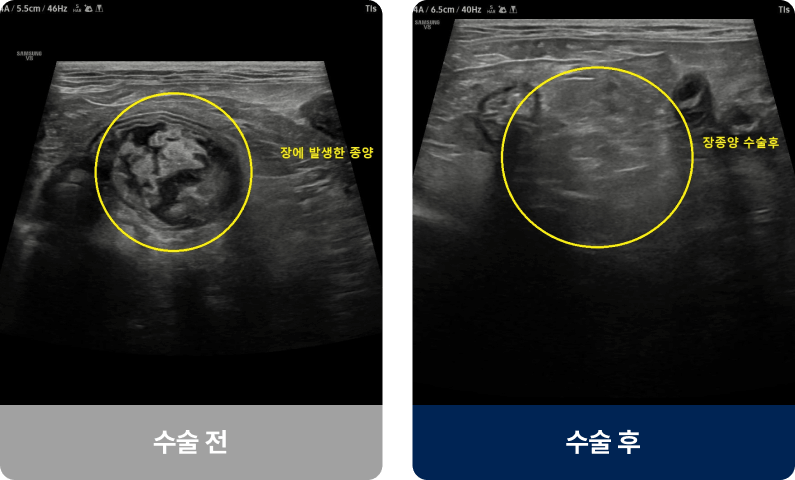

간·비장·폐·피부·유선 등 다양한 장기에 비정상 세포 덩어리(종양)가 생긴 상태로, 양성과 악성으로 나뉘며 유전적 요인, 호르몬, 비만 등이 영향을 줄 수 있습니다. 노령견에게 발병률이 높으며, 몸에 만져지는 혹·식욕 저하·기력 저하·복부 팽만·기침 증상을 보입니다.

외과적 치료법(수술적 치료)

| 종양 절제술 | 광범위 절제술 | 기관 절제·재건술 | |

|---|---|---|---|

| 수술개요 | 종양 부위만 선택적으로 절제 |

종양 주변 정상 조직까지 절제 |

장기에 생긴 종양 절제 후 기능 재건 |